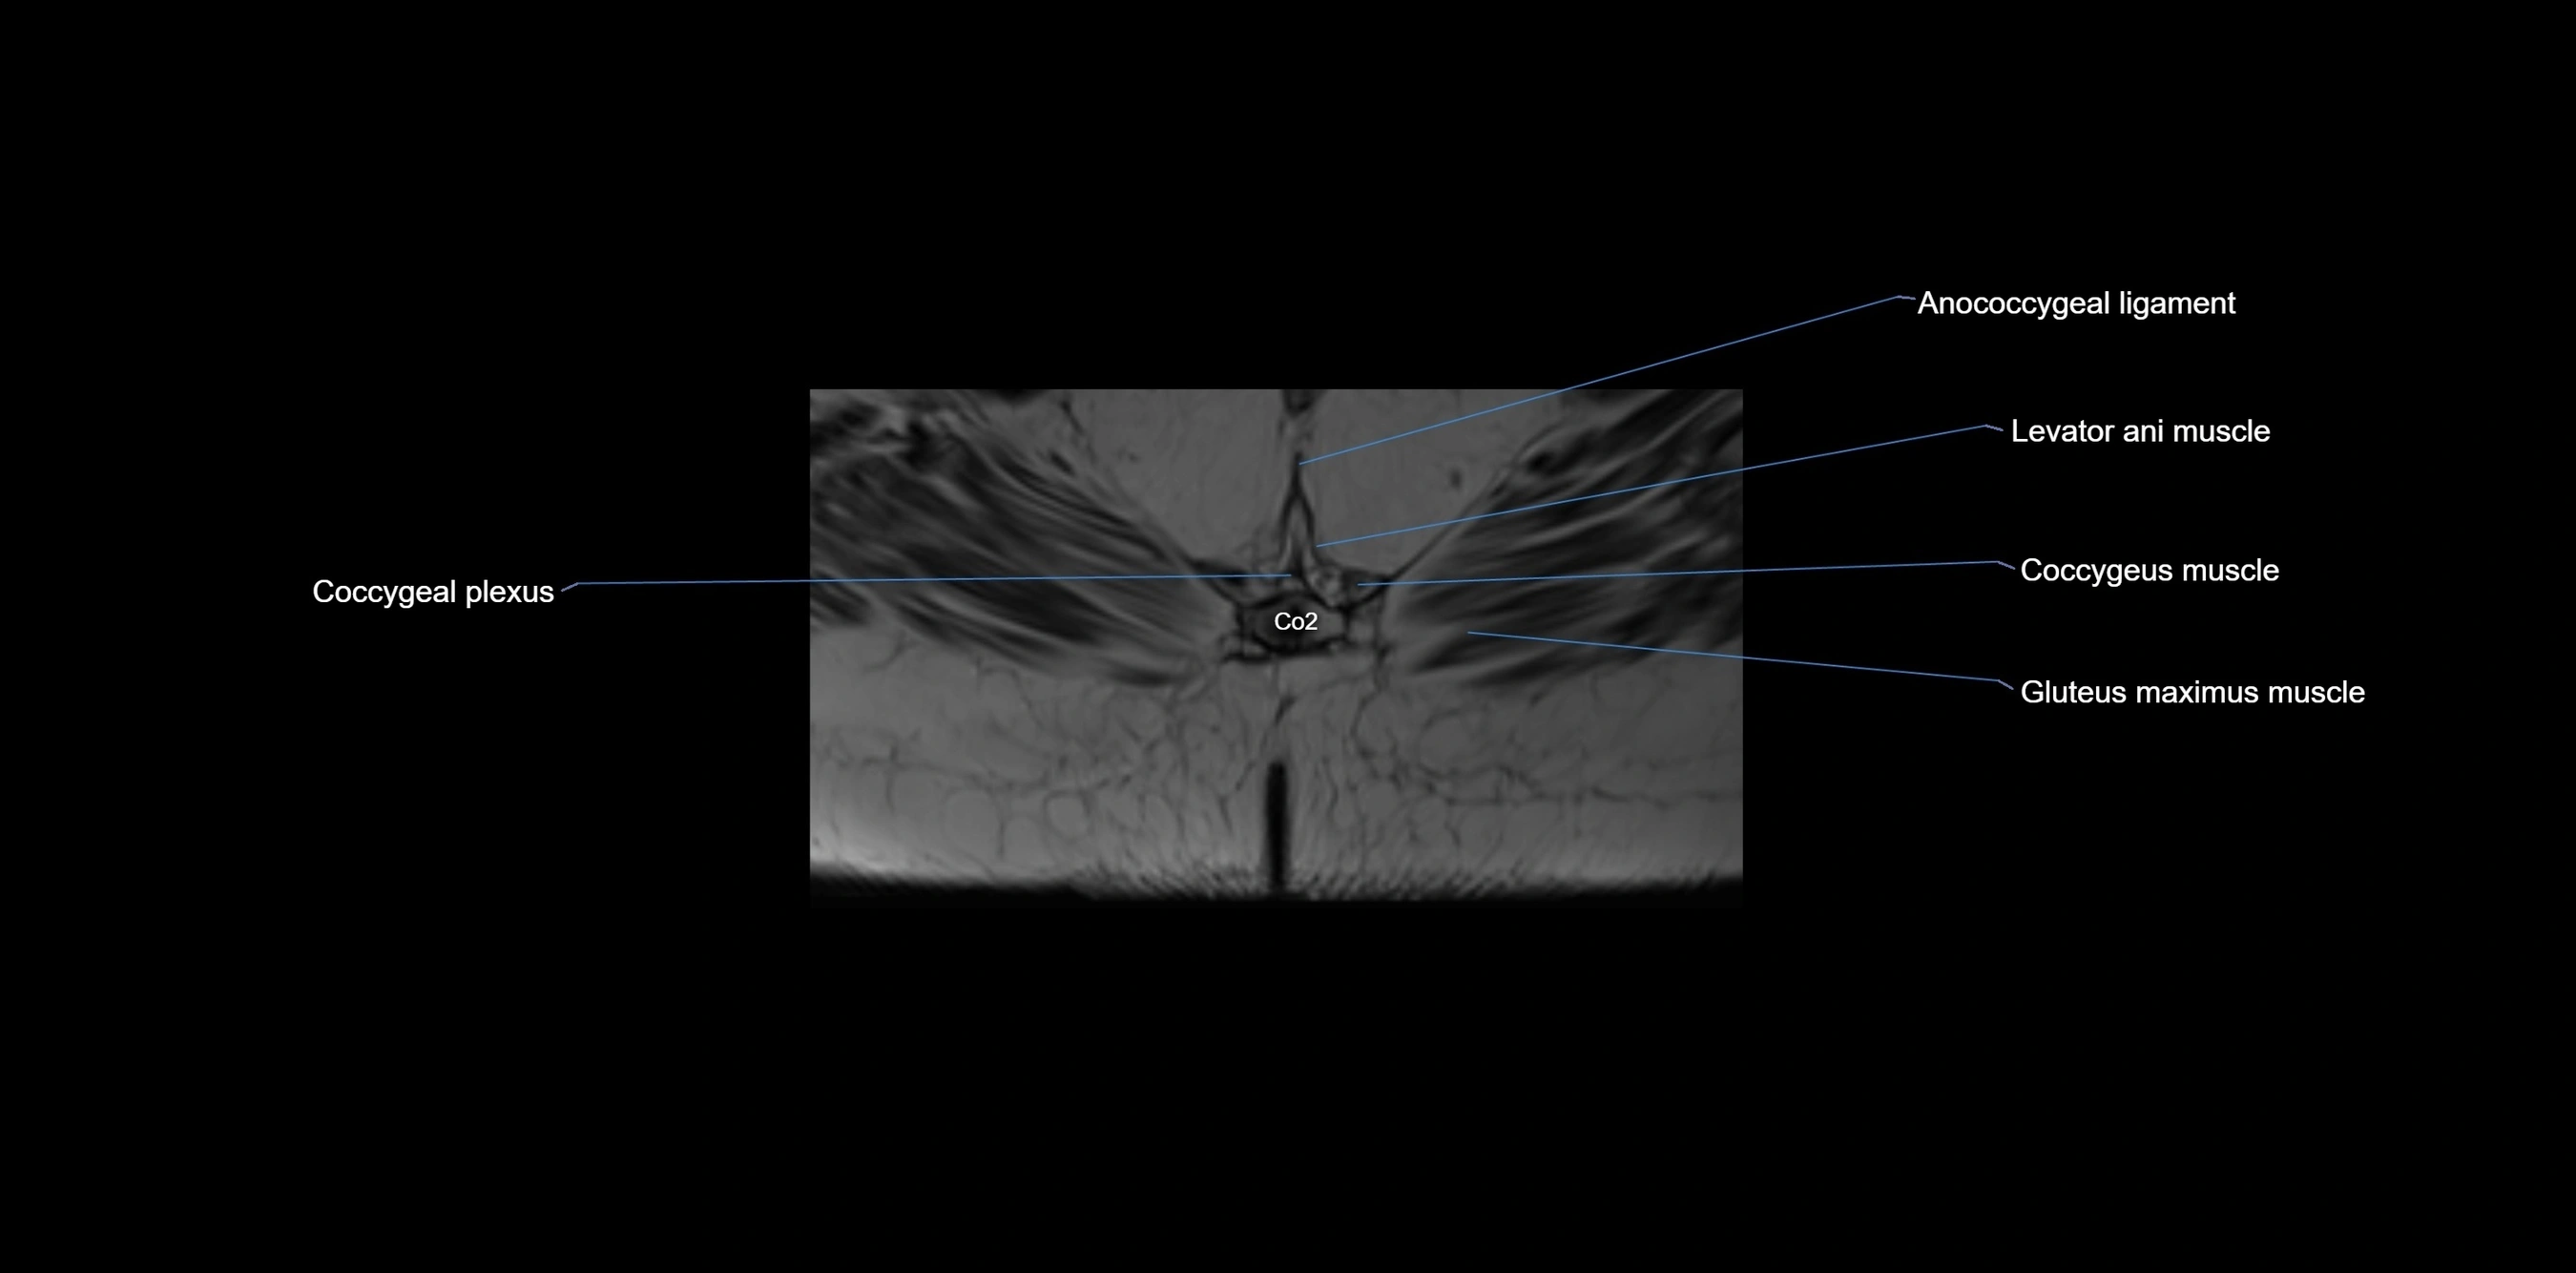

MRI image

image